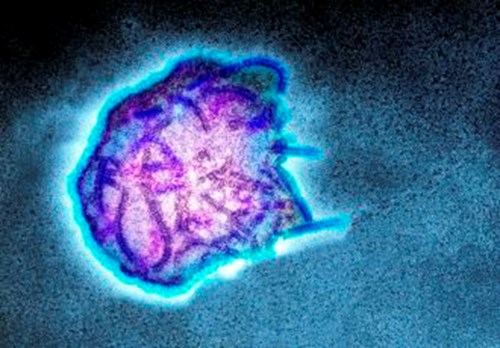

Measles

The measles virus is highly contagious and infects millions of individuals worldwide, causing serious disease in over 10 million children and accounts for about 120,000 deaths each year1. Transmission is predominantly through contaminated aerosols. Infection can be prevented by the administration of measles vaccines either in a monovalent form or in a combination with mumps and rubella – the MMR vaccine. The MMR vaccine is safe and effective as about 97% immunity can be achieved in individuals by the administration of two doses of the vaccine. The vaccine was developed by the attenuation of wild-type Measles virus by in vitro passage in human and chicken cells2.